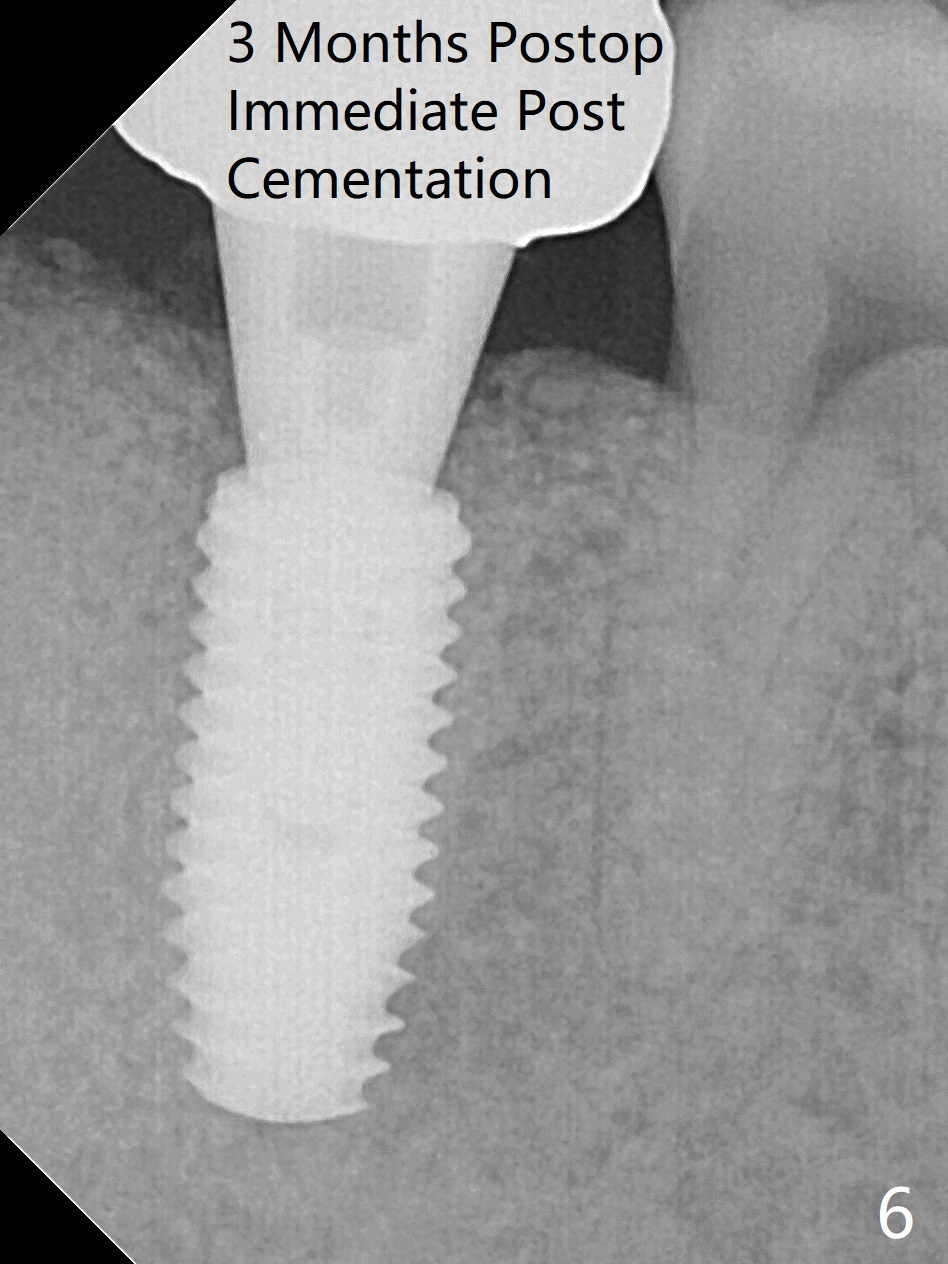

考虑到31号牙严重骨质吸收尤其是远中窝根尖(图一:*),实验室建议钻洞直径要比植体小三号(3.5毫米钻头;5.0毫米植体),其实行不通,使用4.0毫米钻头后,勉强植入4.5毫米报废植体(图一),阴差阳错:植体进入近中牙槽窝,植体四周都有骨壁包绕,包括远中:中隔(S)。最后为了使用5x11.5毫米植体,必须用4.5毫米钻头和5毫米皮质骨攻螺纹(到第三格,多3毫米,图二);放置基台好像没有就位。使用6毫米profile drill(好像去除舌侧中隔)后,手感基台就位,但是根尖片显示(图三)与图二没有区别(植体太粗,看不清楚植体与基台接触)。放置粘性骨粉后(图四),制作临时牙冠,放置PRF后,衬里多次增加固定和与牙龈密合度。术后医嘱包括手术区不使用水牙线。术后一周复诊询问骨粉游出问题。如果第二下磨牙种植能够进入近中窝,不必使用导板,4.5毫米足够,X光片观察基台就位也容易。术后三个月骨粉好像转变成正常骨质(图五,六, 30 Ncm)。